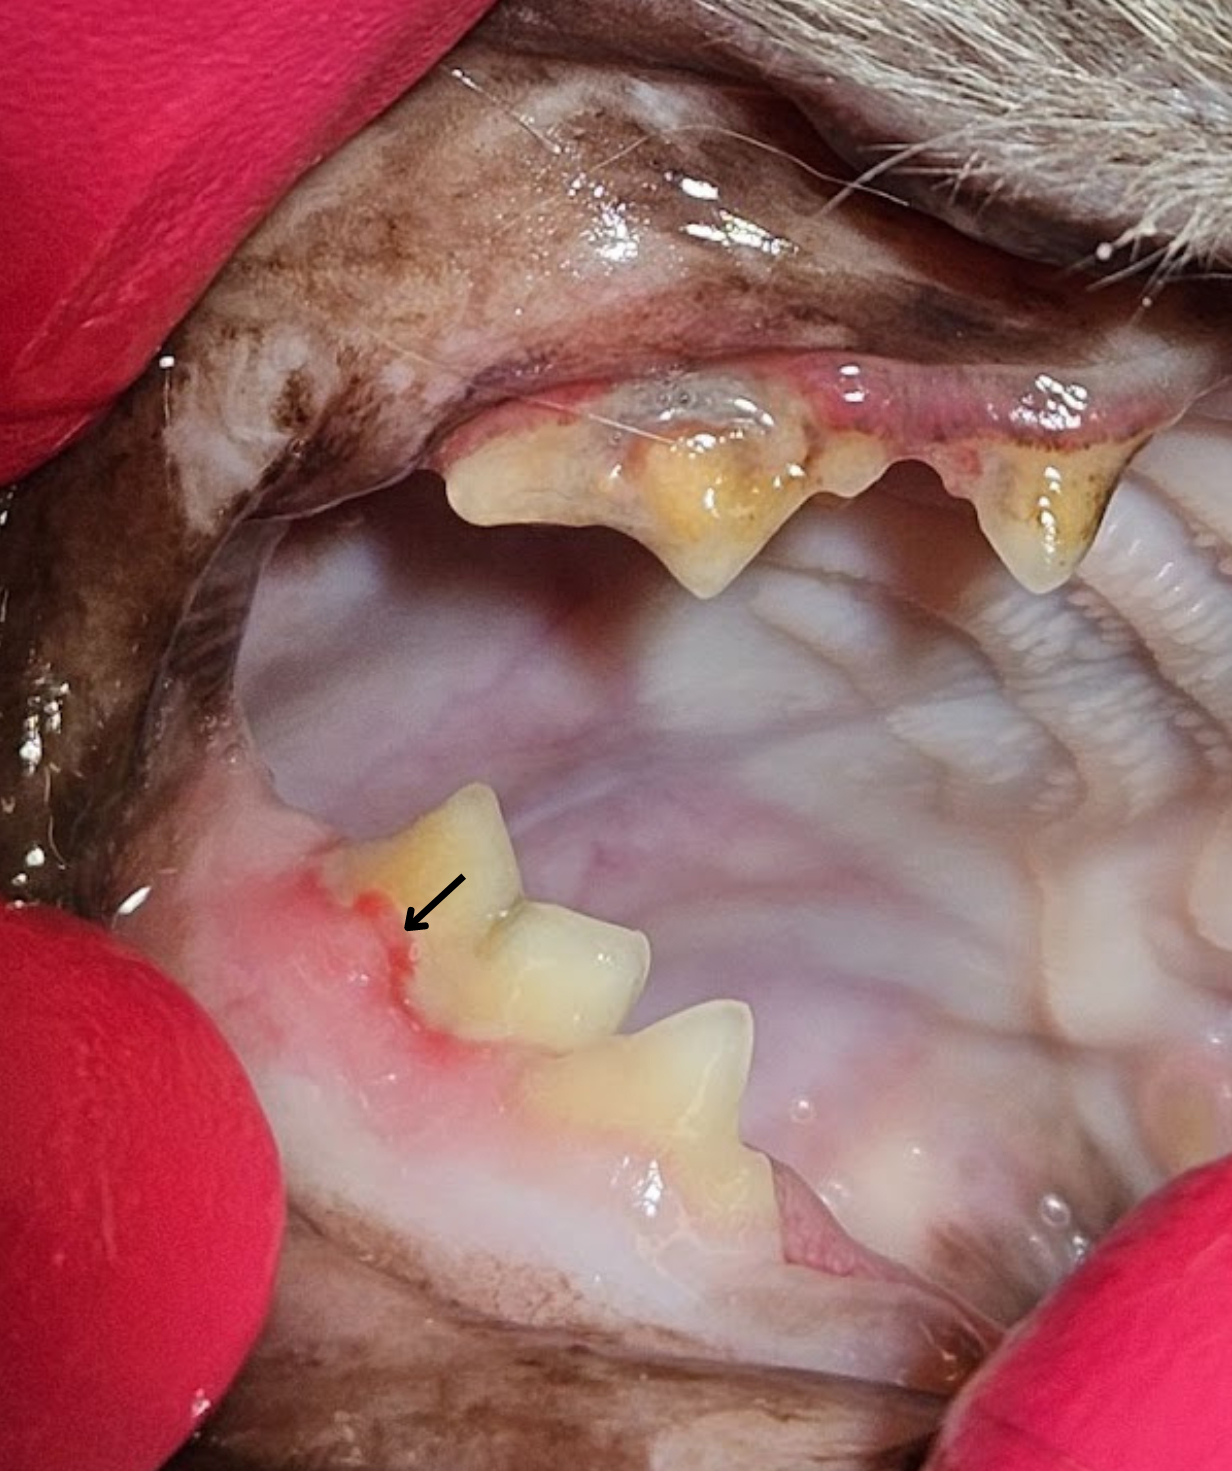

During the COHAT procedure, leons teeth were individually examined and charted, and full mouth X-rays were taken to assess his dental health comprehensively.

Visual examination and probing revealed significant tartar accumulation, gingival inflammation, and evidence of tooth resorption, particularly in the caudal teeth. The diagnosis of tooth resorption was confirmed with dental x-ray and extraction of these affected teeth was deemed necessary. Dental nerve blocks using bupivacaine at a dose of up to 1mg/kg were administered to ensure pain free extraction of these teeth.

Careful attention was paid to avoid complications such as root fractures or leaving behind any root fragments. Three affected teeth, on the right hand side of the mouth were successfully extracted during the initial COHAT, with plans for a second-stage procedure to address the remaining affected teeth on the left side of the mouth. By breaking down extensive dental procedures into manageable stages, we aim to minimise anaesthesia duration, aiming for a maximum time of 2 hours per procedure. This approach aims to mitigate the risks associated with prolonged anaesthesia, enhancing overall safety. Additionally, this strategy allows for one side of the mouth to heal before addressing the other.